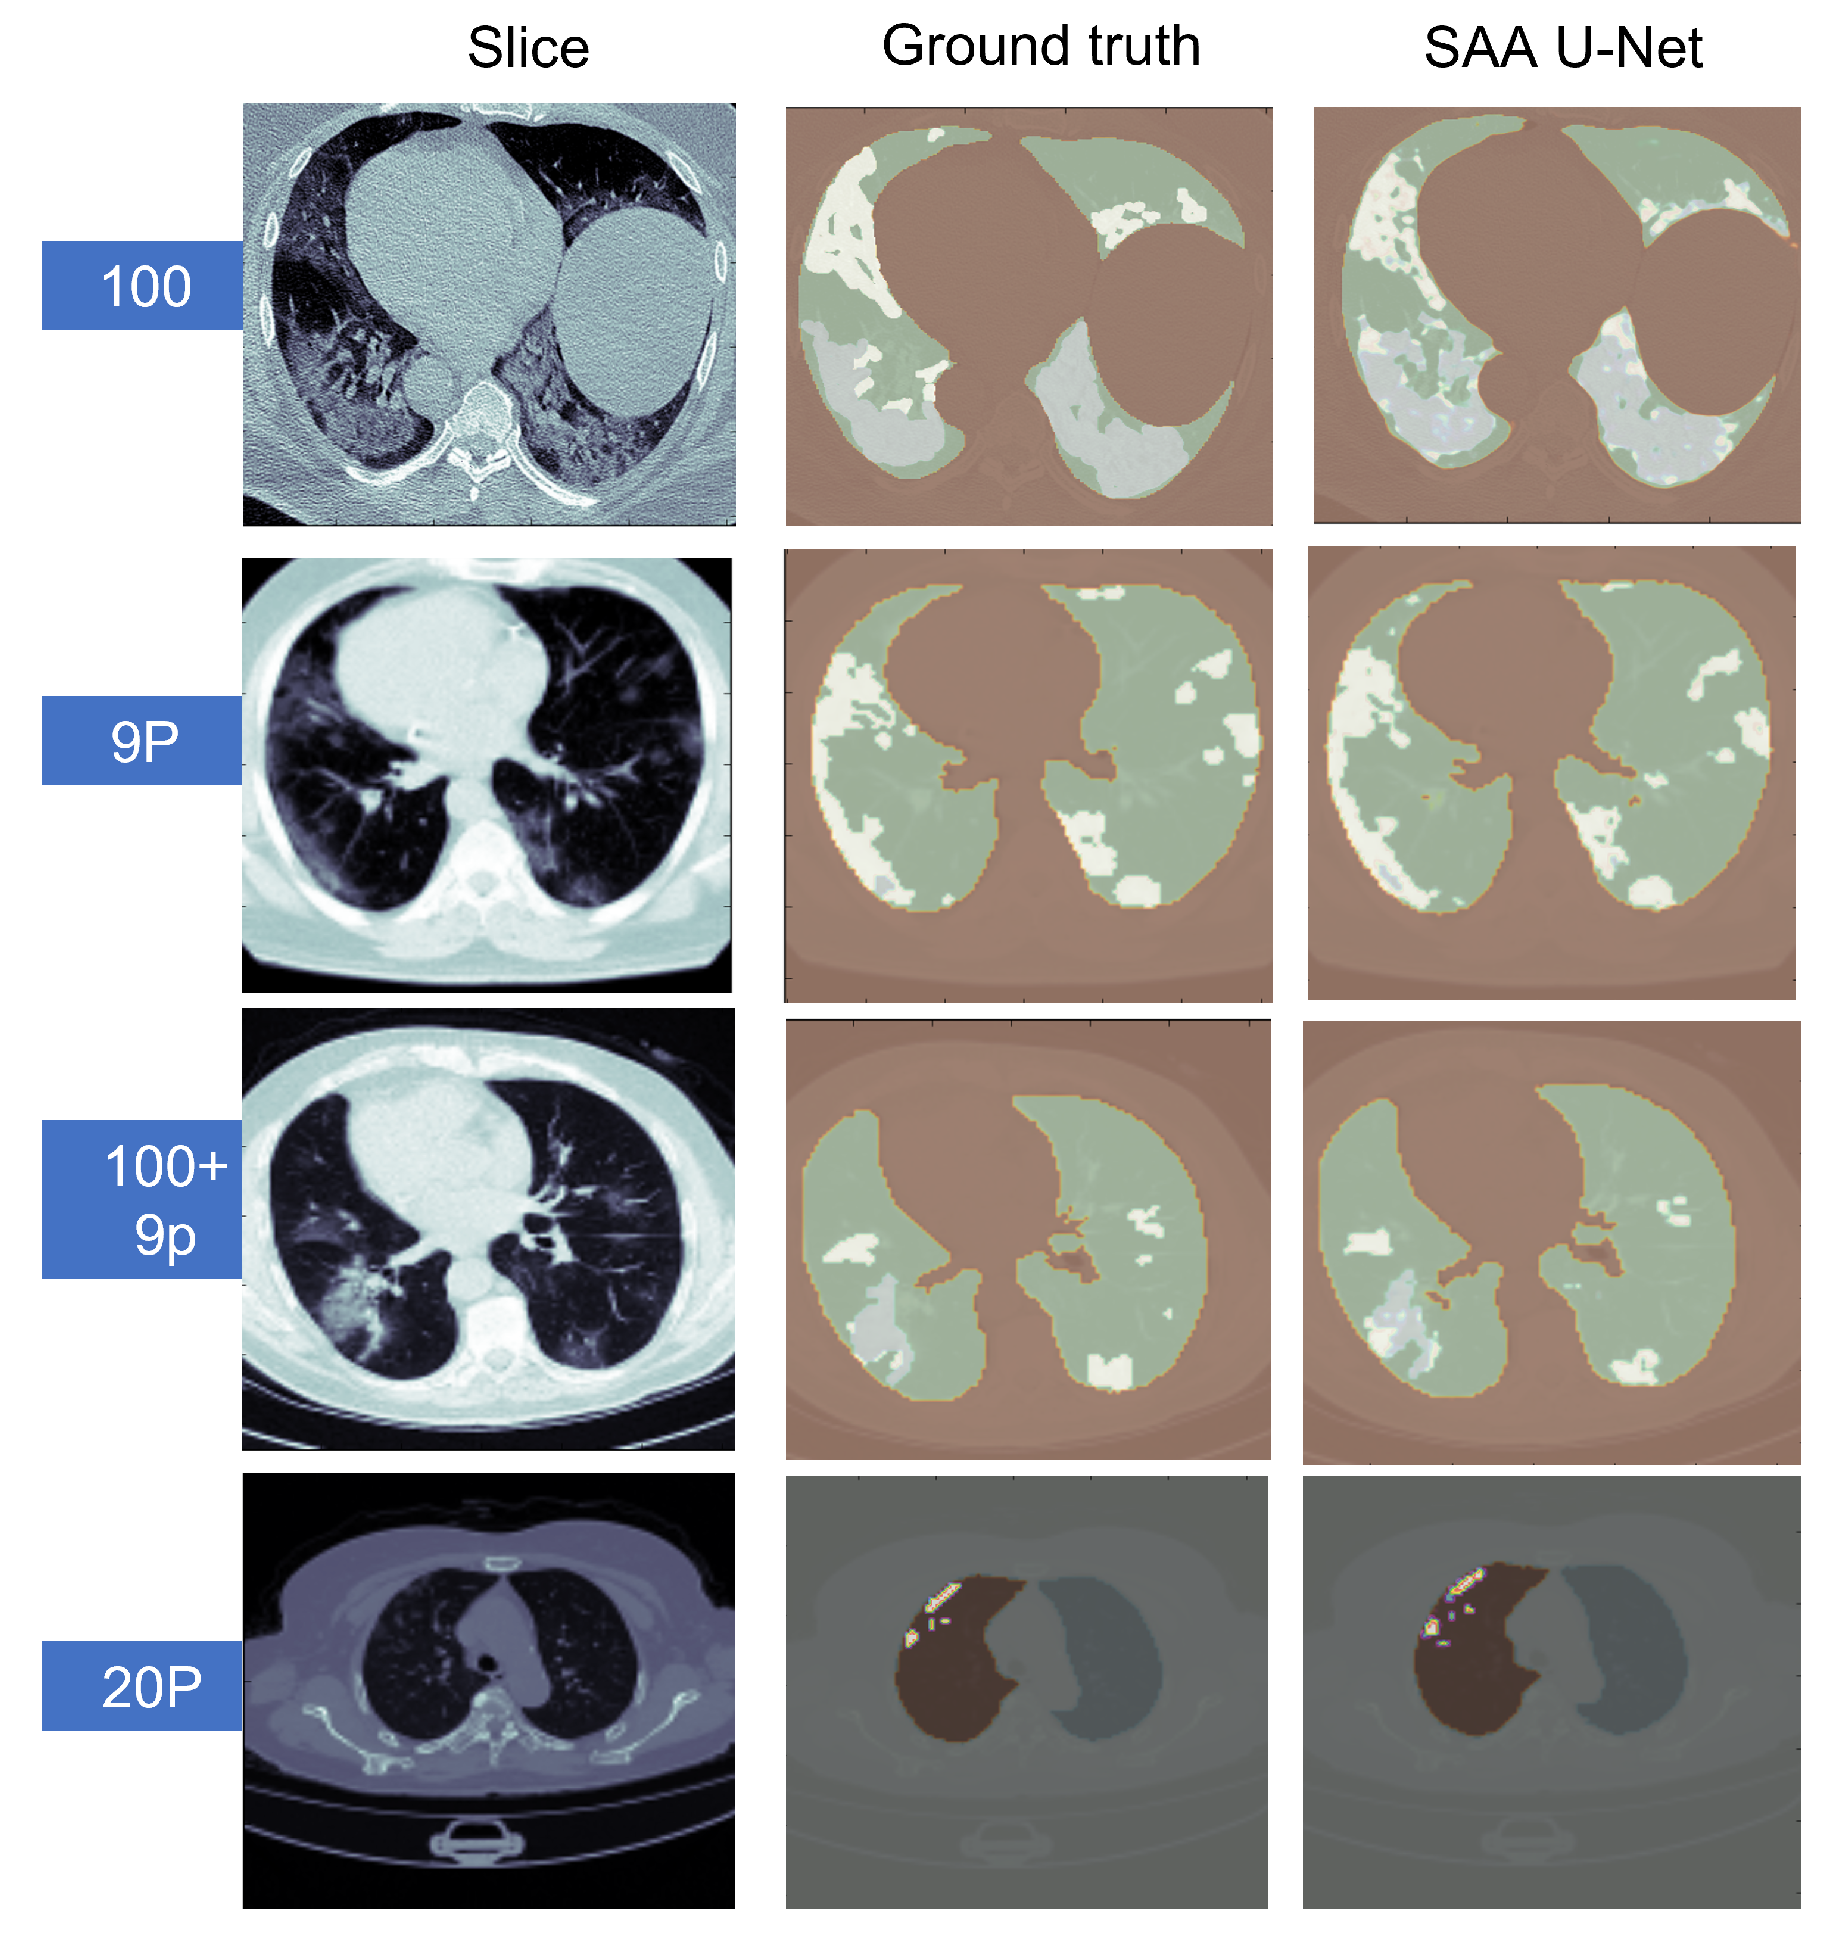

Some sample predicted slices of the three datasets with COVID-19 infection pixels are illustrated in Figure 13. It shows that SAA-UNet had a good prediction of the ground truth. The confusion matrix of each dataset for the SAA-UNet model appears in Figure 14. For the MedSeg dataset, both the GGO and Con classes were confused with the lung class (25% and 11%, respectively). The same trend to a lesser extent was observed for the Radiopaedia 9P dataset as well.

Figure 13.

The predicted CT slices of the best fold for each dataset in multi-class segmentation. In the first three datasets, white is for GGO, grey is for consolidation, green is for lungs, and brown is for the background. For the last dataset, white is for infection, brown for the left lung, grey for the right lung, and lighter greyfor the background.